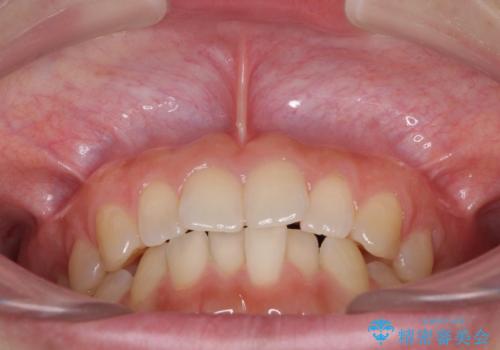

インプラントによる補綴治療とインビザライン矯正

- 抜歯が必要と診断された奥歯を気にして来院された患者様です。

抜歯の上インプラントによる補綴治療を行うこととなりましたが、前歯の叢生も気になるとのことで並行して矯正治療を行うこととしました。

歯列不正は軽微であったので、インビザラインによる矯正治療とし、矯正治療中にインプラント埋入を行う予定としました。

痛みがないので、ボロボロのまま放置していましたが、抜歯後は汚れが溜まりにくくなりスッキリとしたようです。

前歯のデコボコも解消され、ブラッシングが楽になりました。